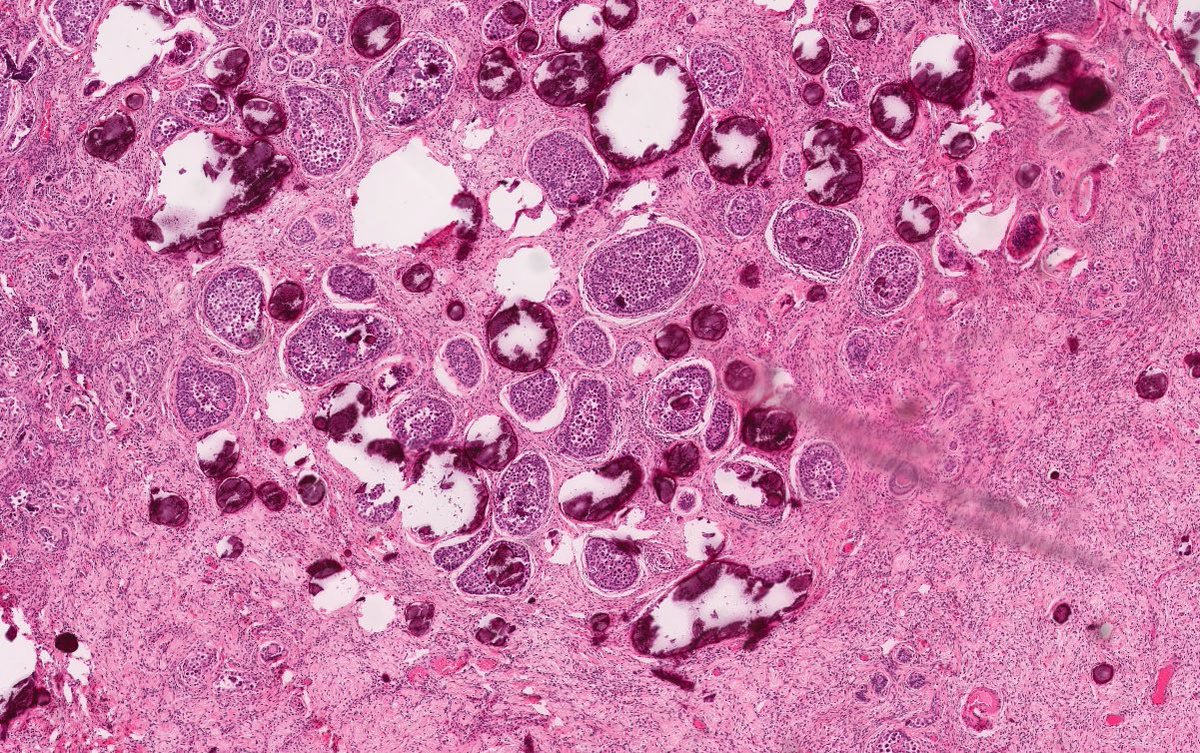

Melanoma can occur in Mucosal Sites like Rectum, Sinonasal, Vaginal Wall I always found this interesting because we usually associate it 🦀 with skin ☀️ Melanocytes are Neural Crest Derived 👶 and they migrate to the mucosa (as well as skin). #pathx #embryology #peds

Melanoma can occur in Mucosal Sites like Rectum, Sinonasal, Vaginal Wall I always found this interesting because we usually associate it 🦀 with skin ☀️ Melanocytes are Neural Crest Derived 👶 and they migrate to the mucosa (as well as skin). #pathx #embryology #peds